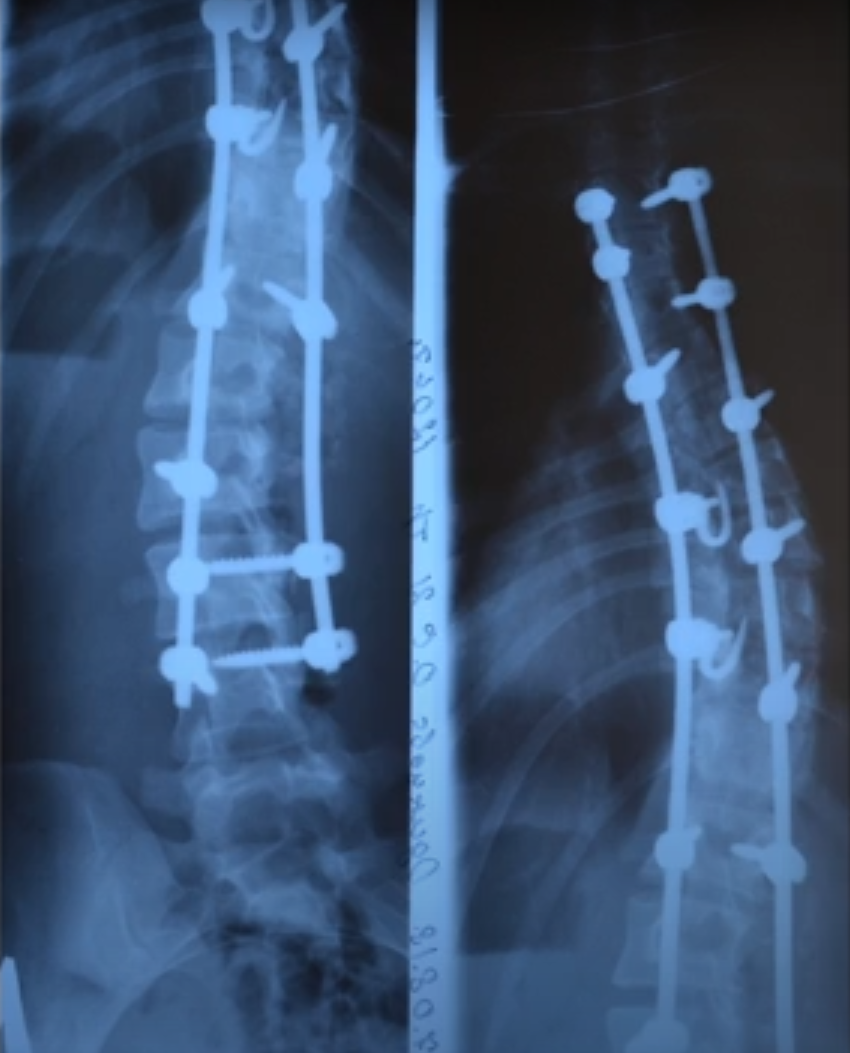

Пациентка была прооперирована. Спустя двое суток после операции подняли девушку. Спустя ещё сутки выполнили рентген, на котором видно, что искривление 30 градусов, то есть в 3 раза улучшилась ситуация. У вершины искривления спинной мозг очень плотно прилегает к ножкам дуг, поэтому установили крючки из разработанной нами системы LSZ. Эта система помогает провести нормальную коррекцию быстро и безопасно. Наложили косметические швы. На седьмые сутки пациента выписали.

Рентгеновские снимки до/после операции. Уменьшение искривления в 3 раза.